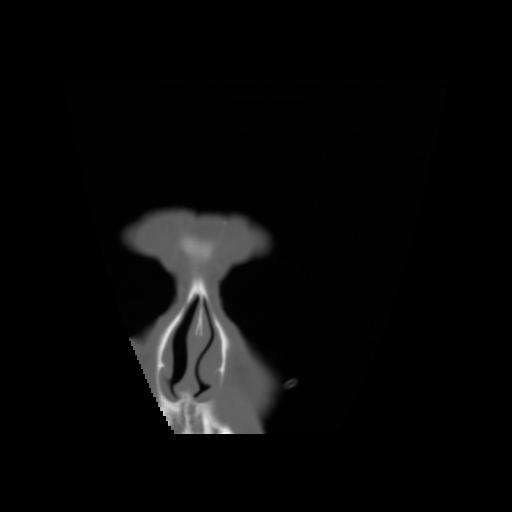

5 CEREBRO,,Coronal,3.000,CEREBRO,Coronal,